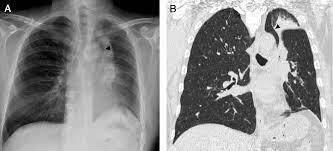

Es el aumento de la atenuación pulmonar, por ocupación del espacio aéreo alveolar por sangre, pus, agua o exudado:

Consolidación/alveolar

¿Cómo se ve la consolidación en Rx?

Radioopacidad irregular y mal definida

¿Cómo se ve la consolidación en TC?

Hipodensidad irregular y mal definida

Es la principal causa de consolidación:

Neumonía